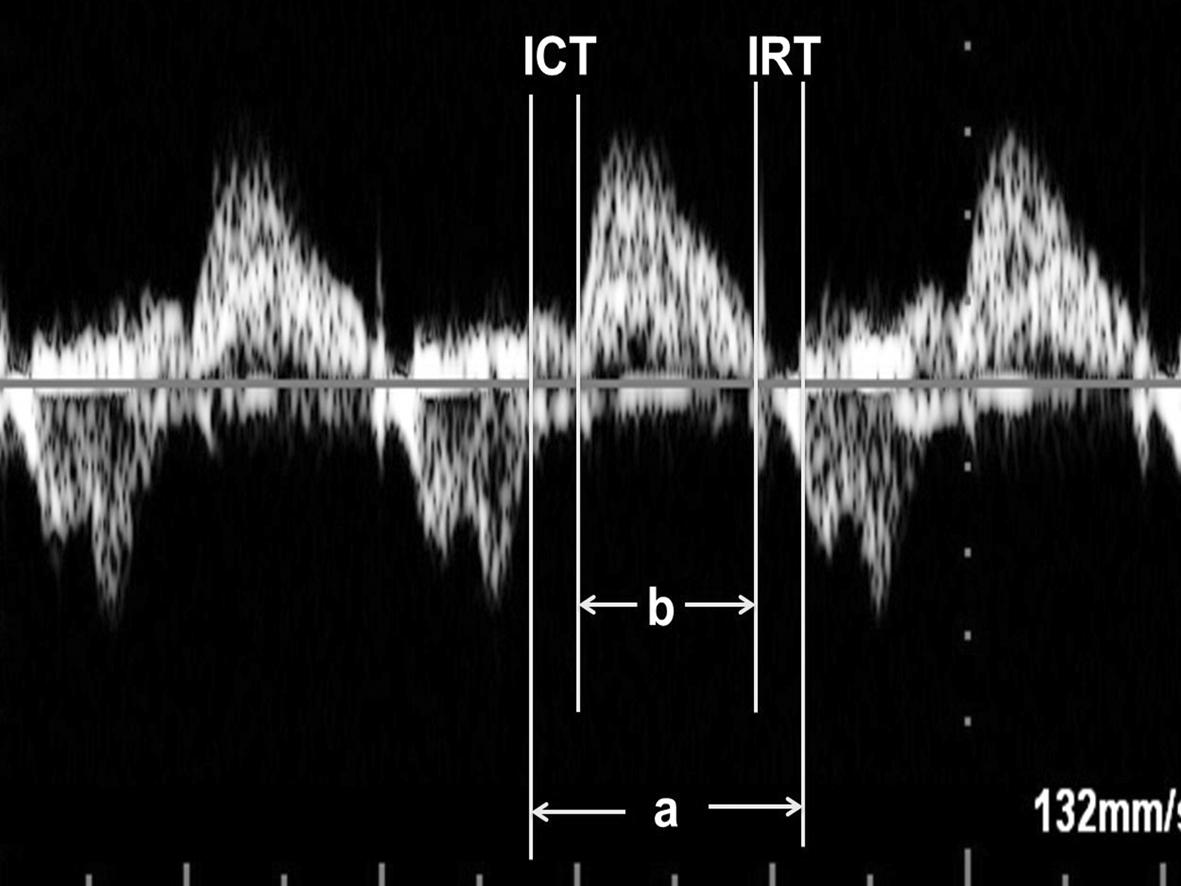

STDI检查可以通过等容收缩时间(ICT)、射血时间(ET)和等容舒张时间(IRT)计算心肌做功指数(MPI, Tei指数),并且通过STDI获得MPI较使用频谱多普勒检查获得MPI更可靠。

3.胎儿心脏功能的综合评价 MPI(Tei指数)可以对胎儿心脏功能作出综合评估。使用PTDI或频谱多普勒检查均可获得MPI。

(1)MPI计算:①频谱多普勒检查心脏时,显示胎儿心脏五腔观,取样门放置在二尖瓣前叶远端和LV流出道结合部位,可以同时获得MVO血流和LV流出道血流,测量二尖瓣血流频谱前一心动周期A峰结束到下一心动周期E峰开始的时间间期,记为A,测量LV流出道血流时间为B,MPI = (A - B) / B;也有作者采取分别在MVO远端和AO瓣口获取血流频谱计算MPI的方法。②胎儿心脏TDI检查时测量显示Ea峰起点至Aa结束的时间(a)以及Sa持续时间(b),通过(a-b)/b获得MPI(图8、图9)。

图8 血流频谱法测量Tei指数

图9 改良的血流频谱法测量Tei指数

(2)注意事项:采用(a - b)/b的方法计算MPI简单方便,但不能区分等容收缩期和等容舒张期,二者还是有一定的不同的;在频谱多普勒检查采用不同的心动周期分别获取等容收缩期/等容舒张期和射血时间会由于心率的差异影响MPI计算的准确性。采取单一心动周期可以在一个屏幕上同时显示心室充盈及其射血时间可以避免心率对计算结果的影响。由于解剖结构的特点,该方法尤其适用于胎儿LV。在胎儿心脏四腔观上,采取3~4mm的取样门宽,多可以在同一幅图像上获得理想的LV流入道和流出道血流频谱,或还可获得RV流入道和流出道血流频谱;适当调节仪器增益条件和显示屏显示条件,准确、清晰地显示血流速度曲线或瓣环活动曲线可以准确地确定心脏活动时相,以确保MPI计算的准确性。